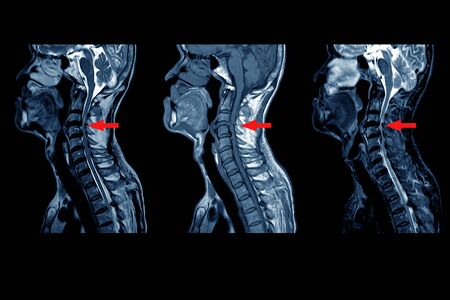

Resonancia Magnética

La resonancia magnética es la prueba que mejor nos ayuda a estudiar la patología cervical. Con una resonancia podremos valorar si hay hernias discales, infecciones o tumores, también valoraremos como se encuentran las estructuras nerviosas o el grado de artrosis que tenemos.